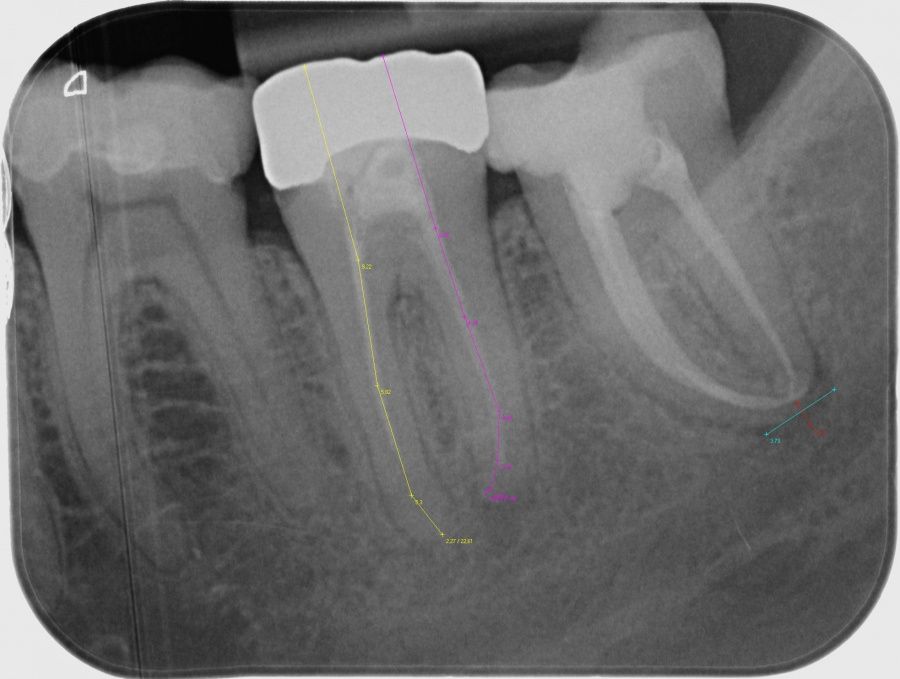

Die Behandlung gliedert sich in mehrere Sitzungen auf. Um eine richtige Diagnose zu ermöglichen, sowie auch um die Behandlung zu planen, sind Röntgenbilder notwendig. Die Behandlung kann durch eine Betäubungsspritze weitestgehend schmerzfrei ablaufen. Undichte Kronen müssen abgenommen werden. Insuffiziente Füllungen und durch Karies erweichte Zahnsubstanz werden entfernt. Fehlende Anteile des Zahnes müssen oft durch eine Aufbaufüllung ergänzt werden (präendodontischer Aufbau).

Damit der Zahn während der Behandlung trocken und sauber bleibt, muss dieser isoliert werden, meistens mit einem Gummituch (sog. Kofferdam). Um genau bis zur Wurzelspitze arbeiten zu können, ist die genaue Längenbestimmung jedes Kanals durch ein elektronisches Verfahren (Elektrometrie) sehr wichtig. Im Zahninneren noch befindliches Gewebe, altes Wurzelkanalfüllmaterial und Bakterien werden entfernt und mit speziellen Spüllösungen gereinigt. Die Wurzelkanäle werden von innen erweitert und gereinigt. Dazu werden endodontische Metallfeilen mit unterschiedlichen Durchmessern verwendet, meistens in Verbindung mit einem speziellen Gerät. Die maschinelle Aufbereitung findet mit sehr biegsamen Feilen aus einer speziellen Metalllegierung (Nickel-Titan) statt. Nach abgeschlossener Aufbereitung des Wurzelkanalsystems können nun eine medikamentöse Zwischeneinlage und ein provisorischer Verschluss bis zum nächsten Termin folgen.

Bei völliger Beschwerdefreiheit wird das Wurzelkanalsystem getrocknet und mit Guttapercha und einem Zement gefüllt. Eine Röntgenaufnahme muss anschließend zur Kontrolle der korrekten Wurzelkanalfüllung und für Dokumentationszwecke angefertigt werden.